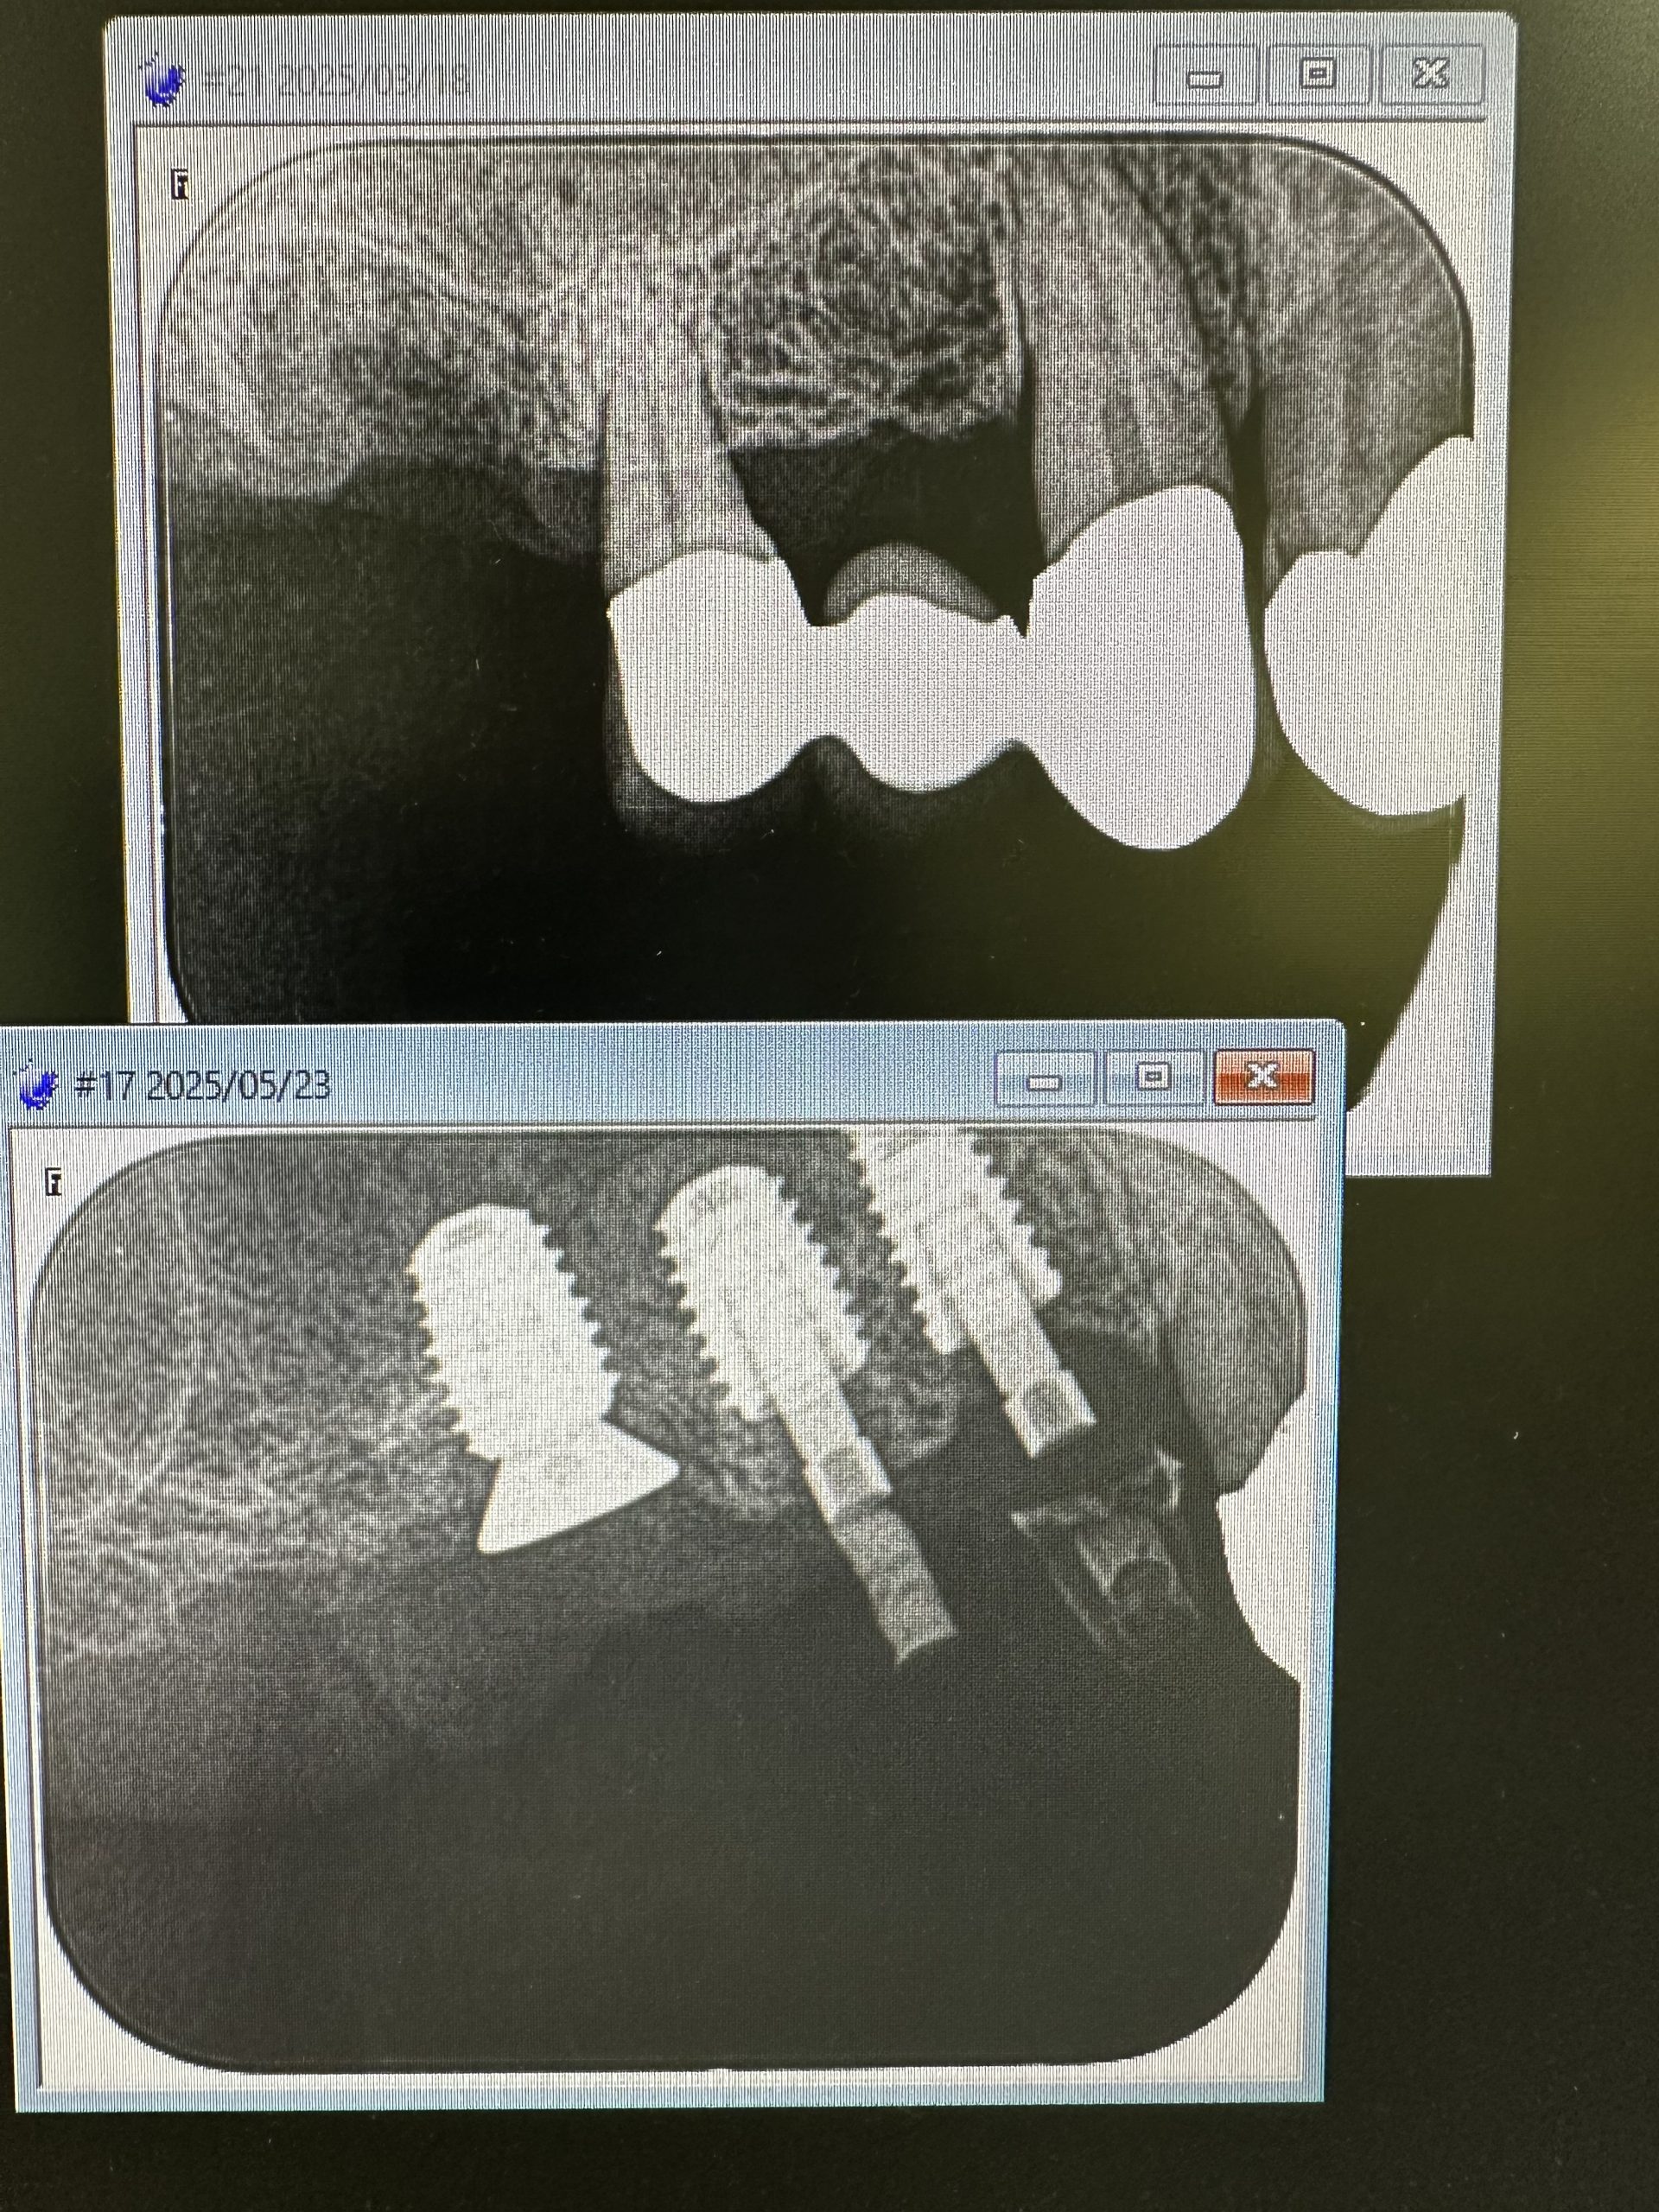

私は、朝からインプラント3本スキャナー印象

昼間からは、危ない動脈近接のソケットリフト

5ミリで骨折、自己採血2本メンブレン挿入

計測値バッチリ75後半👍👌

6から8wで印象、仮歯かなあ